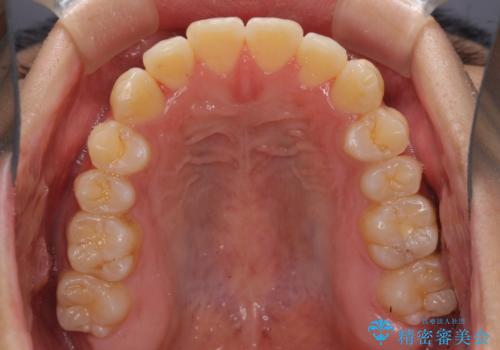

- 前歯のデコボコと若干口元が突出していることを気にして来院された患者様です。

全体的に軽微な叢生が認められ、口元もやや前方に突出していたため、インビザラインでのIPR(歯と歯の間を削る)と歯列全体の後方移動によって歯並びを整えることとしました。

上下ともに歯列の幅が狭かったため、側方に拡大することで前歯のデコボコや突出感を解消するためのスペースを獲得することができました。

歯並びが改善したことはもちろん、咬み合わせの改善まで実感することができ、患者様には大変満足していただけました。